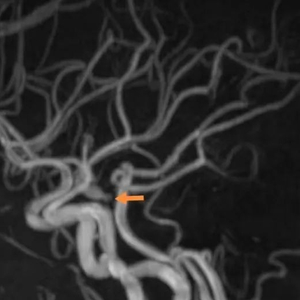

近日,北京市垂杨柳医院神经外科接诊了一位中年女性。入院当天患者突然出现左侧眼睑下垂,视物成双等情况,经神经外科医生刘磊检查,发现患者左侧眼睑不完全下垂,瞳孔左:右=4mm:3mm,对光反射存在,左侧眼球内收受限,其余方向活动正常。刘磊考虑患者左侧动眼神经不全麻痹,左侧后交通动脉瘤先兆破裂可能。紧急为患者加做头颅核磁,核磁血管成像证实为左侧后交通动脉瘤,大小约3*7mm,顶端有子瘤。

▲术前检查,箭头所指为动脉瘤